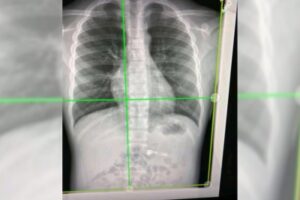

High-energy X-rays show lung vessels altered by Covid-19

X-rays